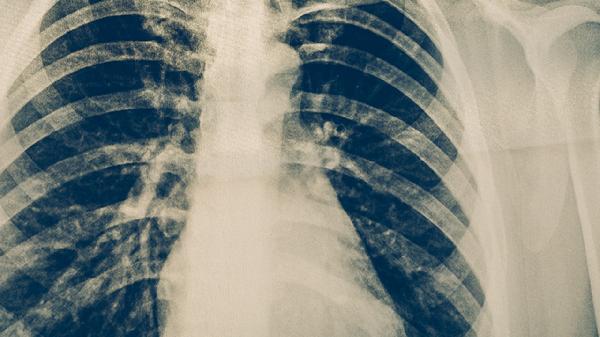

恢复期应避免剧烈运动引发气道痉挛,推荐八段锦等温和锻炼。饮食增加银耳、百合等滋阴食材,忌辛辣油炸食物。若咳嗽超过1个月或出现喘鸣、胸痛需复查胸片,排除黏膜持续损伤或肺不张等并发症。夜间咳嗽明显者可垫高枕头减少气道刺激。